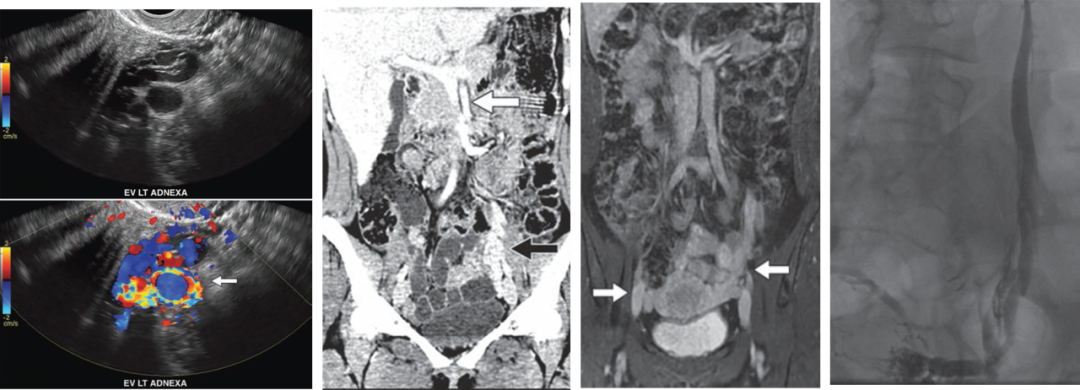

彩色多普勒超声:首选检查,“彩盘蛇”征象提示反流。

CTV / MRV:提供详细解剖结构,指导手术规划。

盆腔静脉造影(DSA):被视为“金标准”,用于制定栓塞策略。

示例(D-IIV)

示例(LOV+LCV)